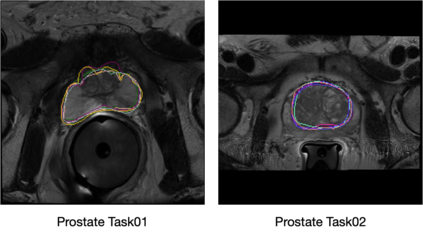

Medical imaging, including MRI, CT, and Ultrasound, plays a vital role in clinical decisions. Accurate segmentation is essential to measure the structure of interest from the image. However, manual segmentation is highly operator-dependent, which leads to high inter and intra-variability of quantitative measurements. In this paper, we explore the feasibility that Bayesian predictive distribution parameterized by deep neural networks can capture the clinicians' inter-intra variability. By exploring and analyzing recently emerged approximate inference schemes, we evaluate whether approximate Bayesian deep learning with the posterior over segmentations can learn inter-intra rater variability both in segmentation and clinical measurements. The experiments are performed with two different imaging modalities: MRI and ultrasound. We empirically demonstrated that Bayesian predictive distribution parameterized by deep neural networks could approximate the clinicians' inter-intra variability. We show a new perspective in analyzing medical images quantitatively by providing clinical measurement uncertainty.